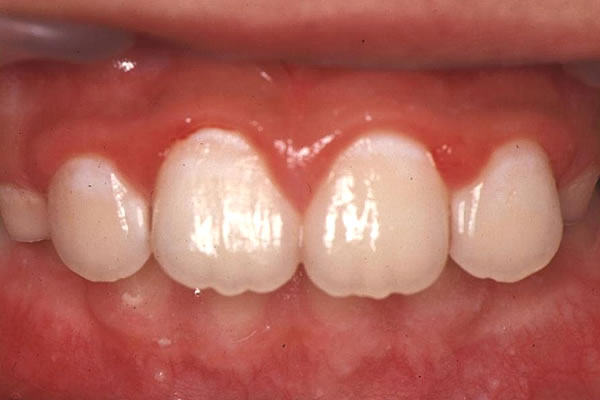

ここに1枚の写真がある。

これは診療室で撮影した小学校2年生のものである。

(図1)

小学校2年生の前歯

さて、この写真を見てあなたはどう思われるだろう?

「歯肉が腫れている。」

「歯頸部が白濁している。」

そんなことから、常時歯頸部には歯垢が付着していると思われる。

また、わずかな出血から、診療室に入る直前に歯を磨いたとも推察される方もおられるだろう。

いずれにせよ、もう少していねいに歯頸部を磨く必要があるというのが一般的な意見だろう。